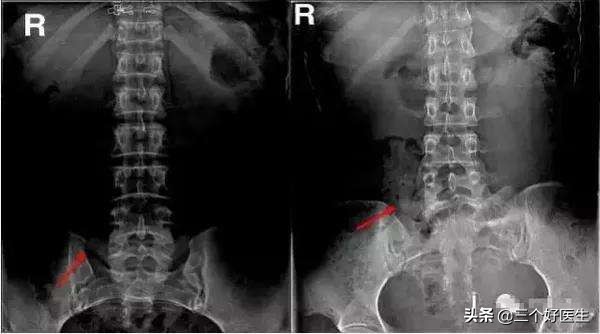

腰椎骶化可以通过X光片来观察(腰椎正位片),不建议首选MR、CT。如下图:

腰椎骶化